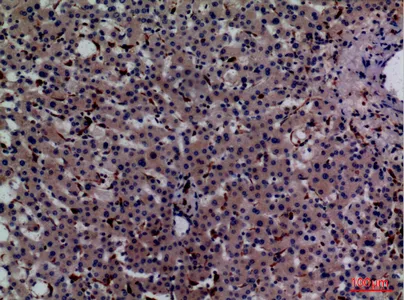

HSP90β (phospho Ser254) Rabbit Polyclonal Antibody

Cat: APRab04808

Size1:50μl Price1:$128

Size2:100μl Price2:$230

Size3:500μl Price3:$980